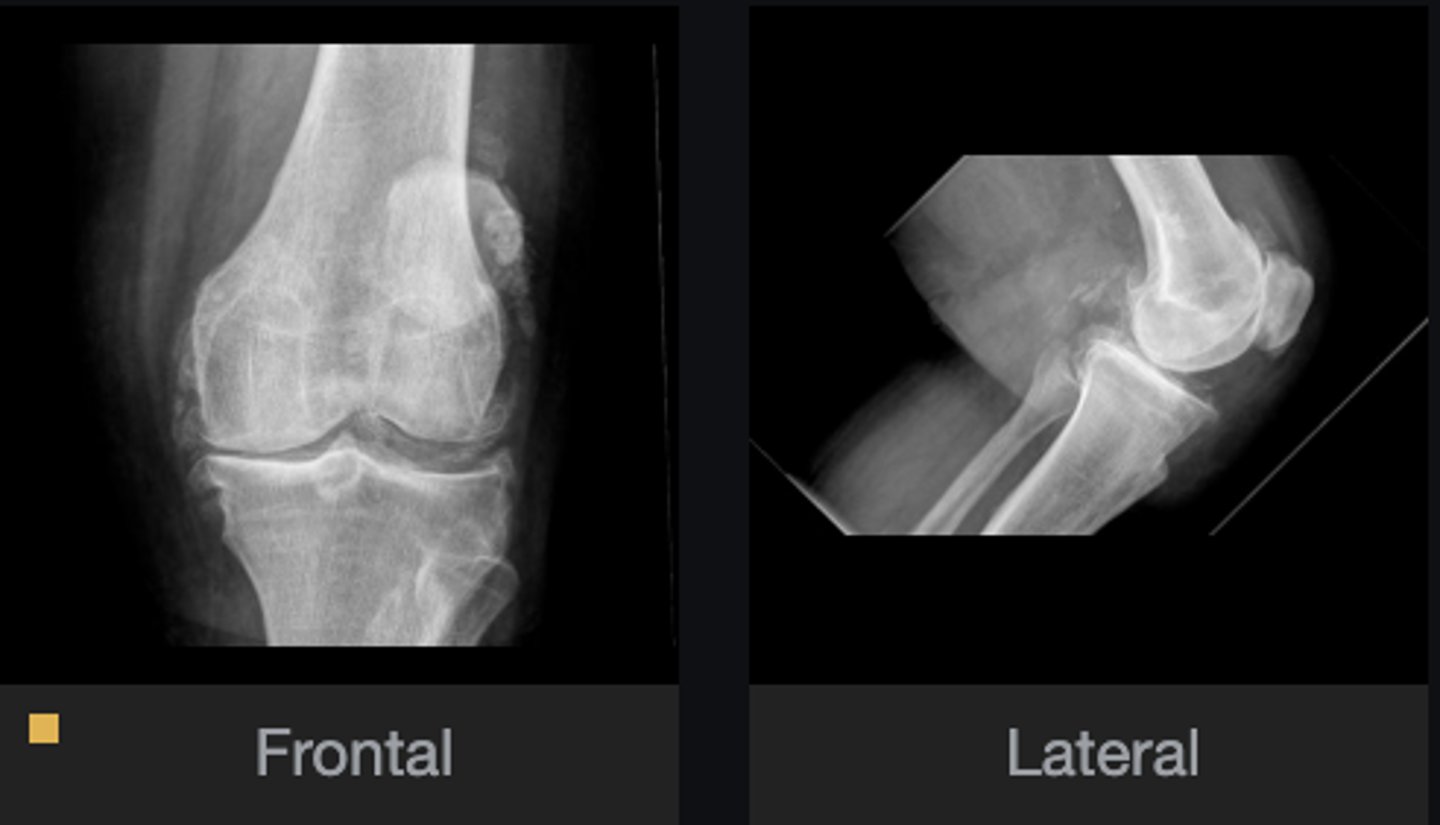

- Calcification of cartilage

- Meniscal calcification

- Non-uniform loss of joint space

- Osteophytes

- Subchondral cysts

- Subchondral sclerosis

- Subluxation

What abnormal findings are present?

CPPD

Most likely diagnosis?